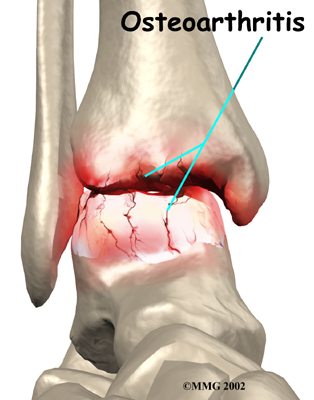

OA is usually considered a type of degenerative arthritis, or wear-and-tear arthritis. Doctors consider OA pretty much the same whether it appears years after an injury to the joint or whether it appears without any history of injury. It behaves more or less the same way.

Injury to a joint, such as a bad sprain or fracture, can cause damage to the articular cartilage. The cartilage can be bruised when too much pressure is exerted on it. This damages the cartilage, although if you look at the surface it may not appear to be any different. The injury to the material doesn't show up until months later. Sometimes the cartilage surface is damaged even more severely, and pieces of the cartilage are ripped from the bone. These pieces do not heal back and usually must be removed from the joint surgically. If not, they may float around in the joint, causing the joint to catch and be painful. These fragments of cartilage may also do more damage to the joint surface.

Once this cartilage is ripped away, it does not normally grow back. Unlike bone, holes in the surface are not simply replaced by the cartilage tissue around the hole. Instead the defects are filled with scar tissue. The scar tissue that forms is not nearly as good a material for covering joint surfaces as the cartilage it replaces. It just can't support weight and isn't smooth like true articular cartilage.

An injury to a joint, even if it does not injure the articular cartilage directly, can alter how the joint works. This is true for a fracture where the bone fragments heal differently from the way they were before the break occurred. It is also true when ligaments are damaged that lead to instability in the joint. When an injury results in a change in the way the joint moves, the injury may increase the forces on the articular cartilage. This is similar to any mechanical device or machinery. If the mechanism is out of balance, it wears out faster.

Over many years this imbalance in the joint mechanics can lead to damage to the articular surface. Since articular cartilage cannot heal itself very well, the damage adds up. Finally, the joint is no longer able to compensate for the increasing damage, and it begins to hurt. The damage occurs well before the pain begins.

Pain is the main problem with arthritis of any joint. This pain occurs at first only related to activity. Usually, once the activity gets underway there is not much pain, but after resting for several minutes the pain and stiffness increase. Later, when the condition worsens, pain may be present even at rest. The pain may interfere with sleep. The joint may swell, fill with fluid, and feel tight, especially following increased activity. As the articular cartilage starts to wear off the joint surface, the joint may squeak when moved. Doctors refer to this sound as crepitation.

OA will eventually affect the motion of a joint. The joint becomes stiff and loses flexibility. Certain movements can become painful, and it may become difficult to trust the joint to hold your weight in certain positions. The body has a pain reflex such that when a joint is put into a position that causes pain the muscles around the joint may stop working without warning. This reflex can cause a person to stumble or even fall when arthritis affects the ankle joint.

When OA has reached a very severe stage, the bone itself under the articular cartilage may become worn away. This can lead to increasing deformities around the joint. In the final stages, the alignment of the bones can begin to form odd angles where they meet at the joint.